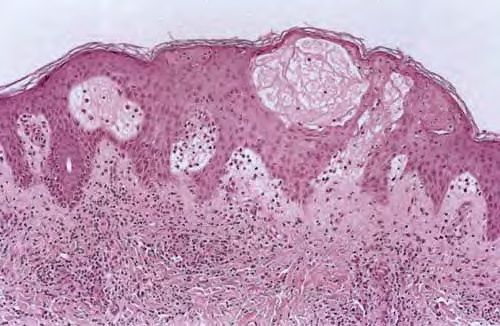

Histopathology The histologic findings vary according to the age of the lesion sampled. Very early lesions show either a normal epidermis or mild spongiosis with focal lymphocyte exocytosis and an underlying mild or occasionally moderate, superficial and deep, perivascular and periadnexal, lymphohistiocytic inflammatory cell infiltrate the lymphocytes have a T-helper phenotype (CD3/CD4 positive). Interestingly, in experimentally induced PMLE lesions, the infiltrate in the first 72 hours postinduction also has a predominant T-helper phenotype but thereafter a mainly T-cytotoxic type (CD3/CD8 positive) . Occasional eosinophils and rare neutrophils may also be found. As lesions progress, there is marked edema of the papillary dermis and more prominent dermal inflammation

in such cases, the histologic picture may resemble cutaneous lupus erythematosus (see next section). Exceptionally, a fairly prominent dermal infiltrate may raise the possibility of lymphoma. In a few cases, the histologic findings may be minimal despite the presence of prominent clinical changes . Pathogenesis. The eruption of PMLE is induced by exposure to UVR, particularly from strong summer sunlight (2,3). Artificial reproduction is less easy, and exact action spectra have not been conclusively determined. Nevertheless, broadly speaking, the responsible wavelengths appear to be UVB in around half of patients and ultraviolet A (UVA) in three quarters, which includes both in one quarter, while visible light has also rarely been incriminated. The eruption itself appears very likely to be a DTH response in view of its pattern of dermal cellular infiltration, cytokine production, and adhesion molecule expression, arguably to UVR-induced, endogenous, cutaneous autoantigen. Further, it appears that a genetically determined impairment of the normal UVR-induced suppression of induction, but interestingly not elicitation, of DTH reactions in the skin is responsible . Differential Diagnosis. The diagnosis is generally apparent from the clinical history, in which sun exposure is nearly always clearly incriminated in causing the typical eruption, provided that the circulating antinuclear and extractable nuclear antibody titers and urinary, stool, and blood porphyrin concentrations are normal. Histologically, PMLE must be differentiated from lupus erythematosus, the porphyrias, AP, Jessner’s lymphocytic infiltrate, cutaneous T-cell lymphoma, chilblains, and rosacea . In cutaneous lupus erythematosus, the interface change is more prominent not only in the epidermis but also in adnexal structures, apoptotic keratinocytes are often seen, and papillary dermal edema is not a feature. In addition, dermal mucin deposition may be seen in lupus and is absent in PMLE. AP usually displays changes secondary to excoriation, variable epidermal hyperplasia, and more prominent lymphocyte spongiosis and exocytosis; however, early lesions in both conditions may show very similar microscopic findings, except that dermal edema is usually absent in AP. In Jessner’s lymphocytic infiltrate, epidermal changes are absent, there is no papillary dermal edema, and the dermal mononuclear cell infiltrate tends to be more prominent. Cutaneous T-cell lymphoma is only rarely included in the differential diagnosis of PMLE, mainly when the dermal infiltrate is prominent; however, the exocytosis of lymphocytes with irregular nuclear outlines is not a feature of the latter, which usually also shows variable spongiosis. The histology of chilblains is almost identical to that of PMLE, particularly when there is prominent papillary dermal edema, but fortunately the clinical setting of each disease usually allows distinction. Rosacea shows no epidermal change, dermal edema is absent, the dermal infiltrate is mild and surrounds superficial small blood vessels and adnexal structures, and focal lymphocytic exocytosis into hair follicles is often seen. |